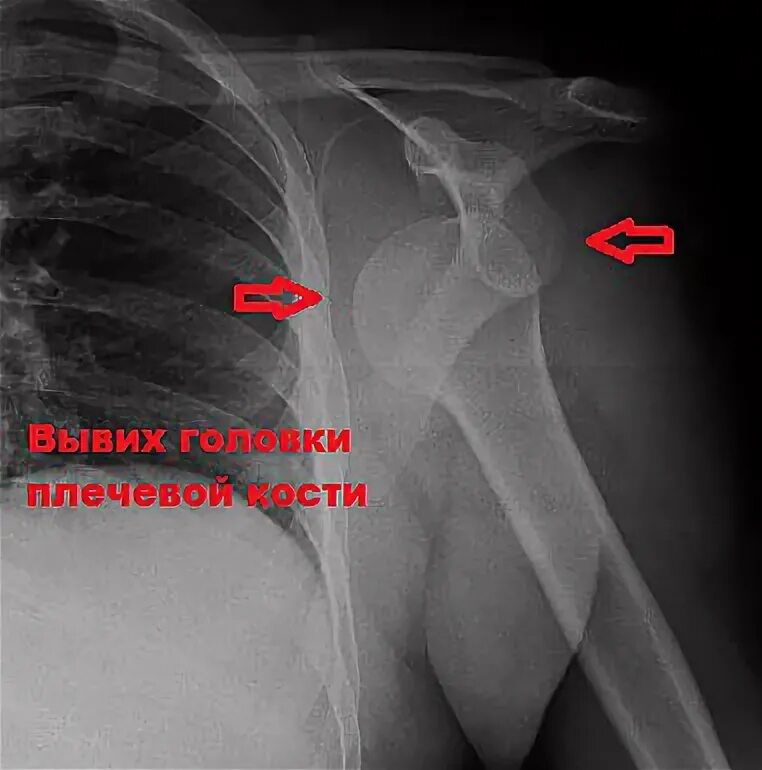

Как долго заживает вывих плеча